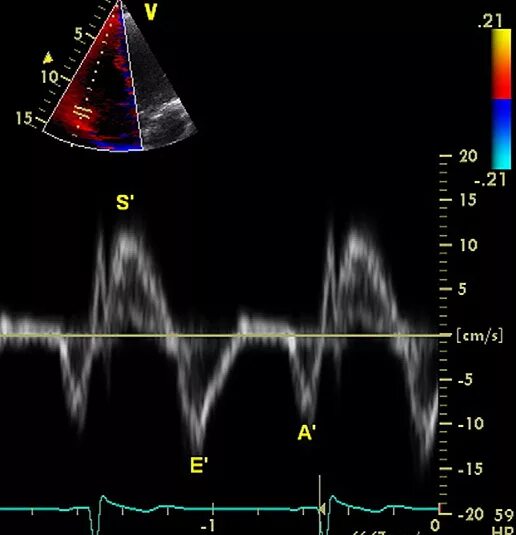

Ддлж по 1 типу по узи сердца